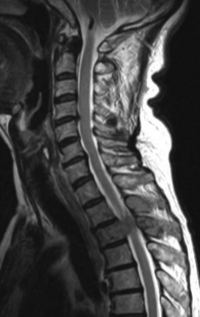

血液所見:赤血球 413 万、Hb 12.0 g/dL、白血球 7,200、血小板 27 万。血液生化学所見:総蛋白 7.3 g/dL、アルブミン 4.2 g/dL、尿素窒素 13 mg/dL、クレアチニン 0.8 mg/dL、AST 40 U/L、ALT 24 U/L、LD 768 U/L (基準 176〜353)、ALP 997 U/L (基準 115〜359)、Na 144 mEq/L、K 4.8 mEq/L、Cl 105 mEq/L。CRP 1.4 mg/dL。胸椎エックス線写真、頸胸椎MRIのT2強調矢状断像及び第3胸椎レベルの水平断像を別に示す。